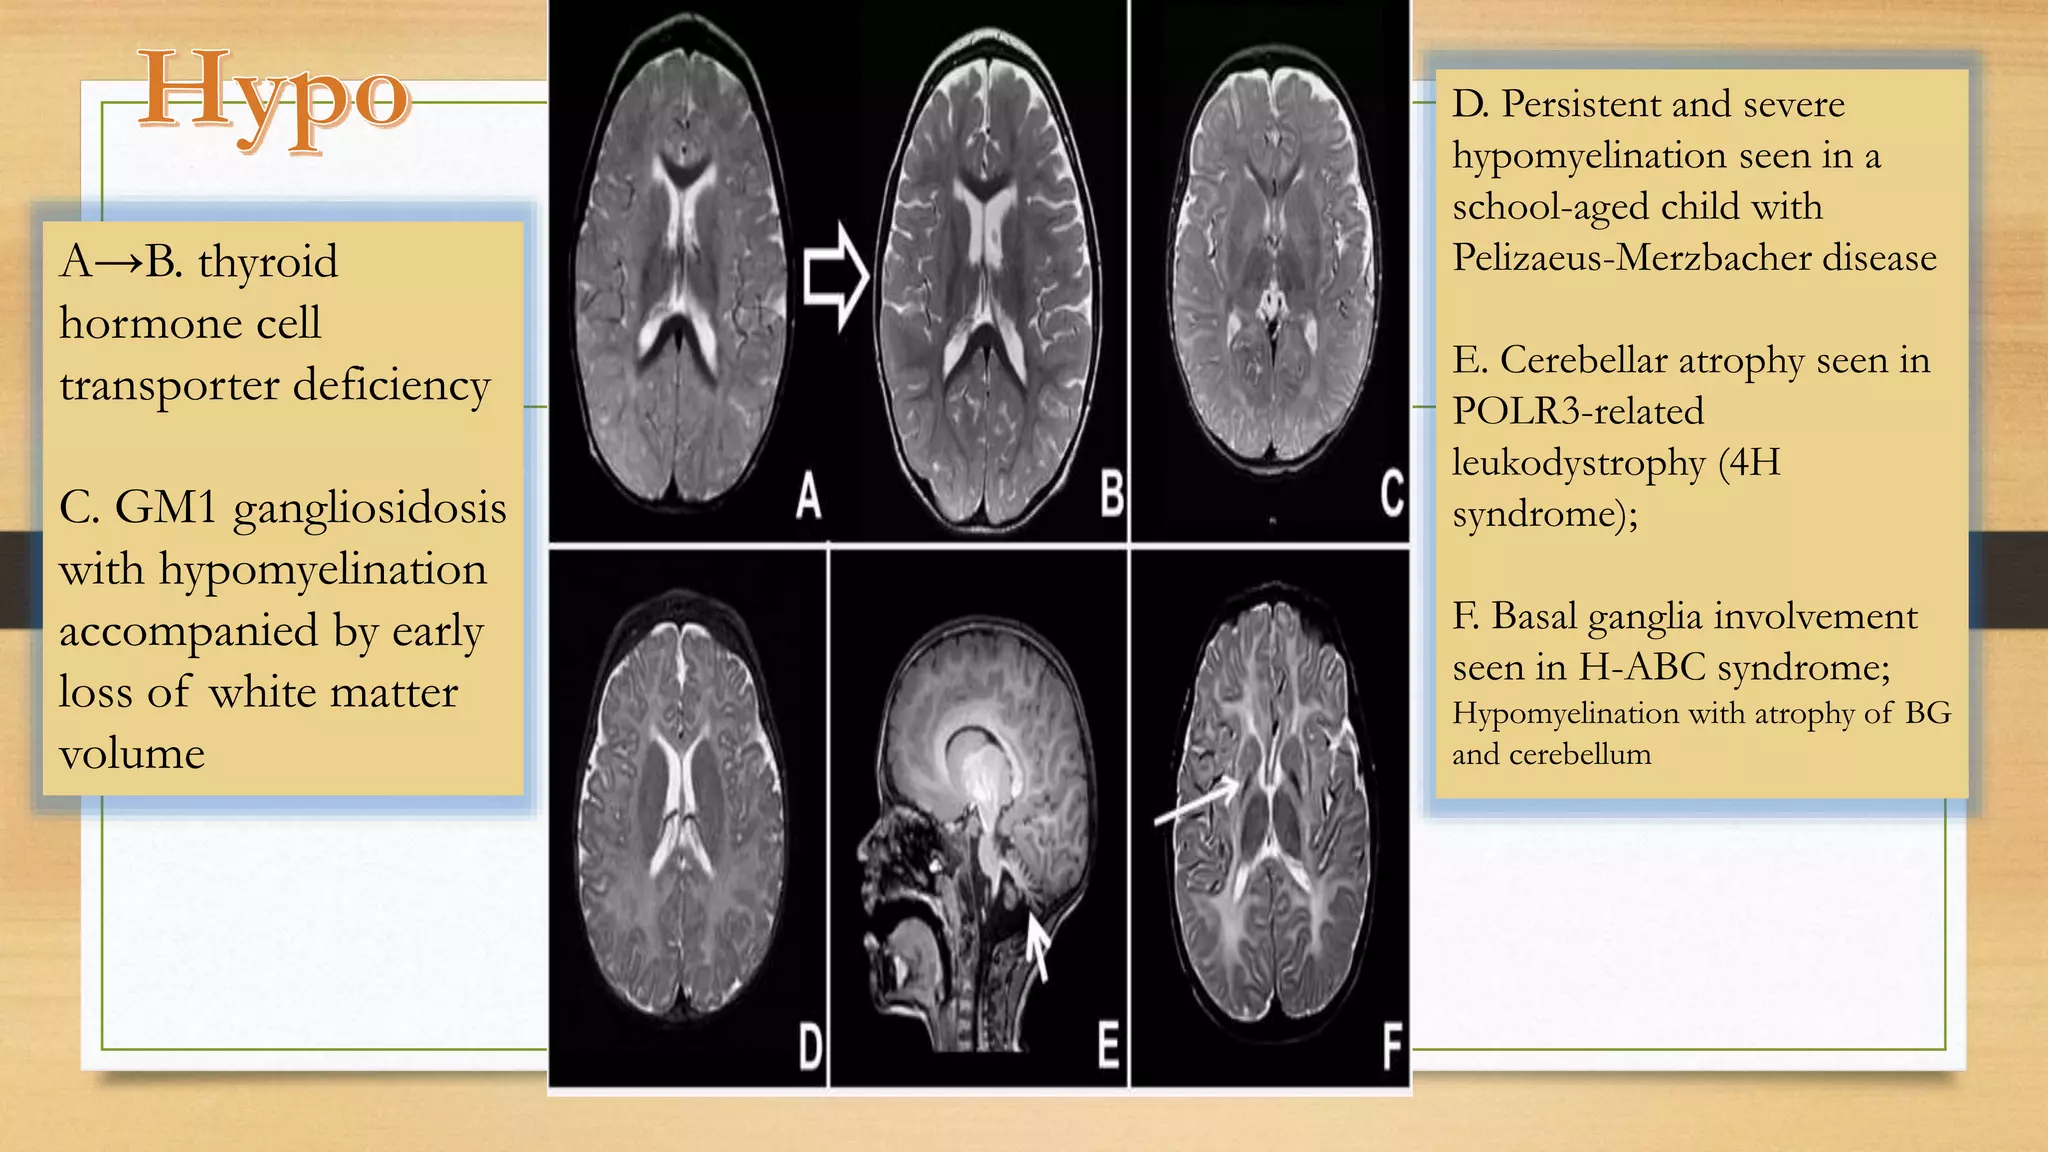

A→B. thyroid

hormone cell

transporter deficiency

C. GM1 gangliosidosis

with hypomyelination

accompanied by early

loss of white matter

volume

D. Persistent and severe

hypomyelination seen in a

school-aged child with

Pelizaeus-Merzbacher disease

E. Cerebellar atrophy seen in

POLR3-related

leukodystrophy (4H

syndrome);

F. Basal ganglia involvement

seen in H-ABC syndrome;

Hypomyelination with atrophy of BG

and cerebellum

A→B. thyroid hormone cell transporterdeficiency C. GM1 gangliosidosis with hypomyelination accompanied by early loss of white matter volume D. Persistent and severe hypomyelination seen in a school-aged child with Pelizaeus-Merzbacher disease E. Cerebellar atrophy seen in POLR3-related leukodystrophy (4H syndrome); F. Basal ganglia involvement seen in H-ABC syndrome; Hypomyelination with atrophy of BG and cerebellum